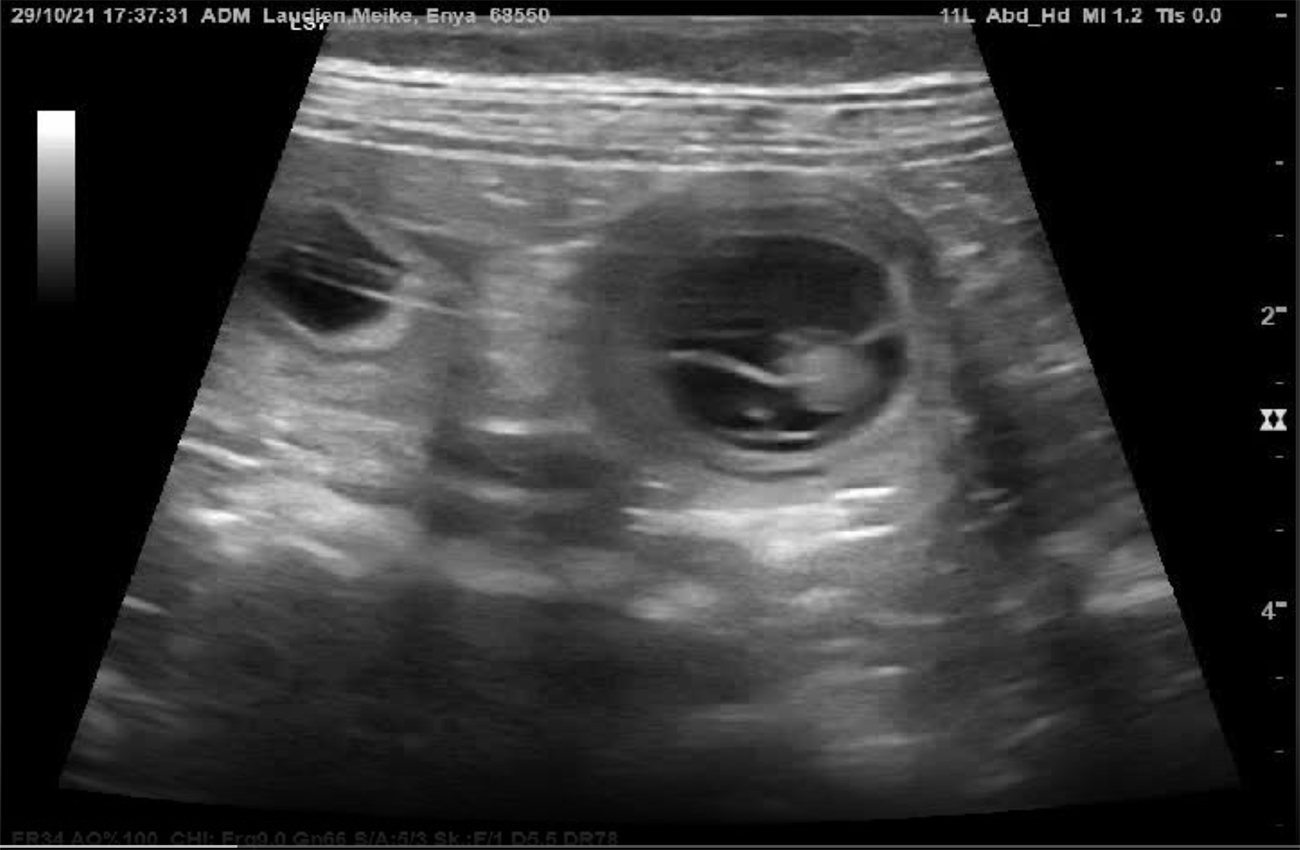

Heute war also der Tag der Tage. Der Tag an dem man Gewissheit bekommt, ob die Hündin aufgenommen hat oder nicht.

Auch wenn in den letzten Tagen einiges für eine Trächtigkeit gesprochen hat, so wollten wir es gerne

von unserem Tierarzt Dr. Marcus Stieger absegnen lassen.

Beim Ultraschall wurden auf Anhieb einige Fruchtanlagen gesichtet. Die genaue Anzahl wollte ich aber nicht wissen.... ein bisschen Spannung soll uns und den Welpeninteressenten schon noch in den kommenden Wochen erhalten bleiben. ;-) |

Wir freuen uns einfach riesig darüber, dass bald wieder kleine J-Racker den Bagalutenhof besetzen werden.